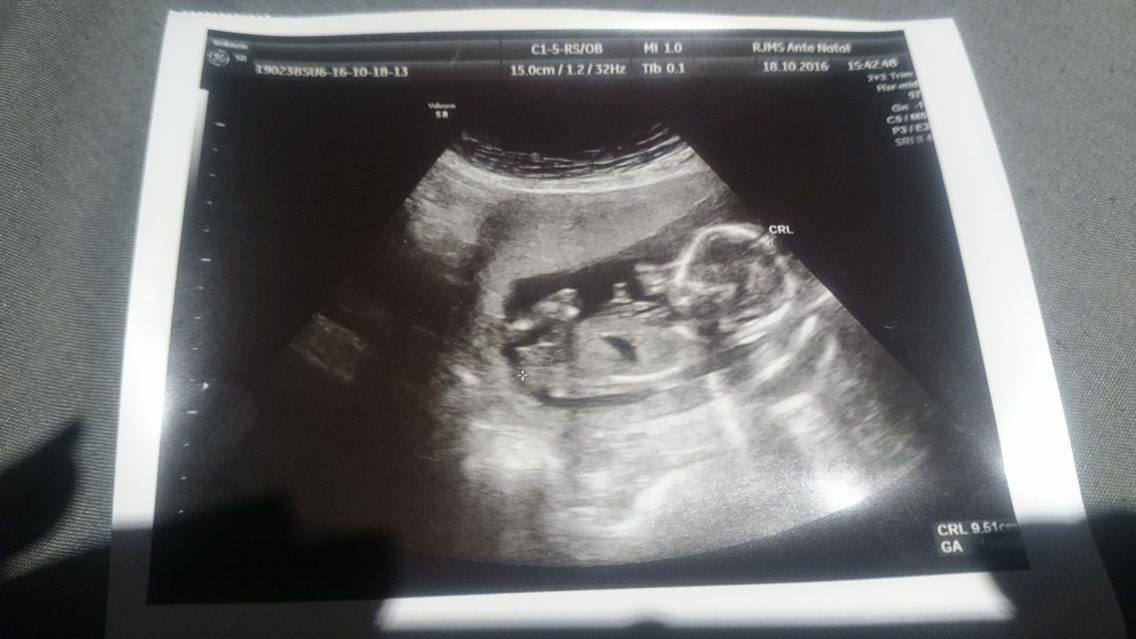

Just wondering if this lil one is showing any clues to being a boy or girl?

15+2 in the scan :)

Looks girly to me.

Girly xxx